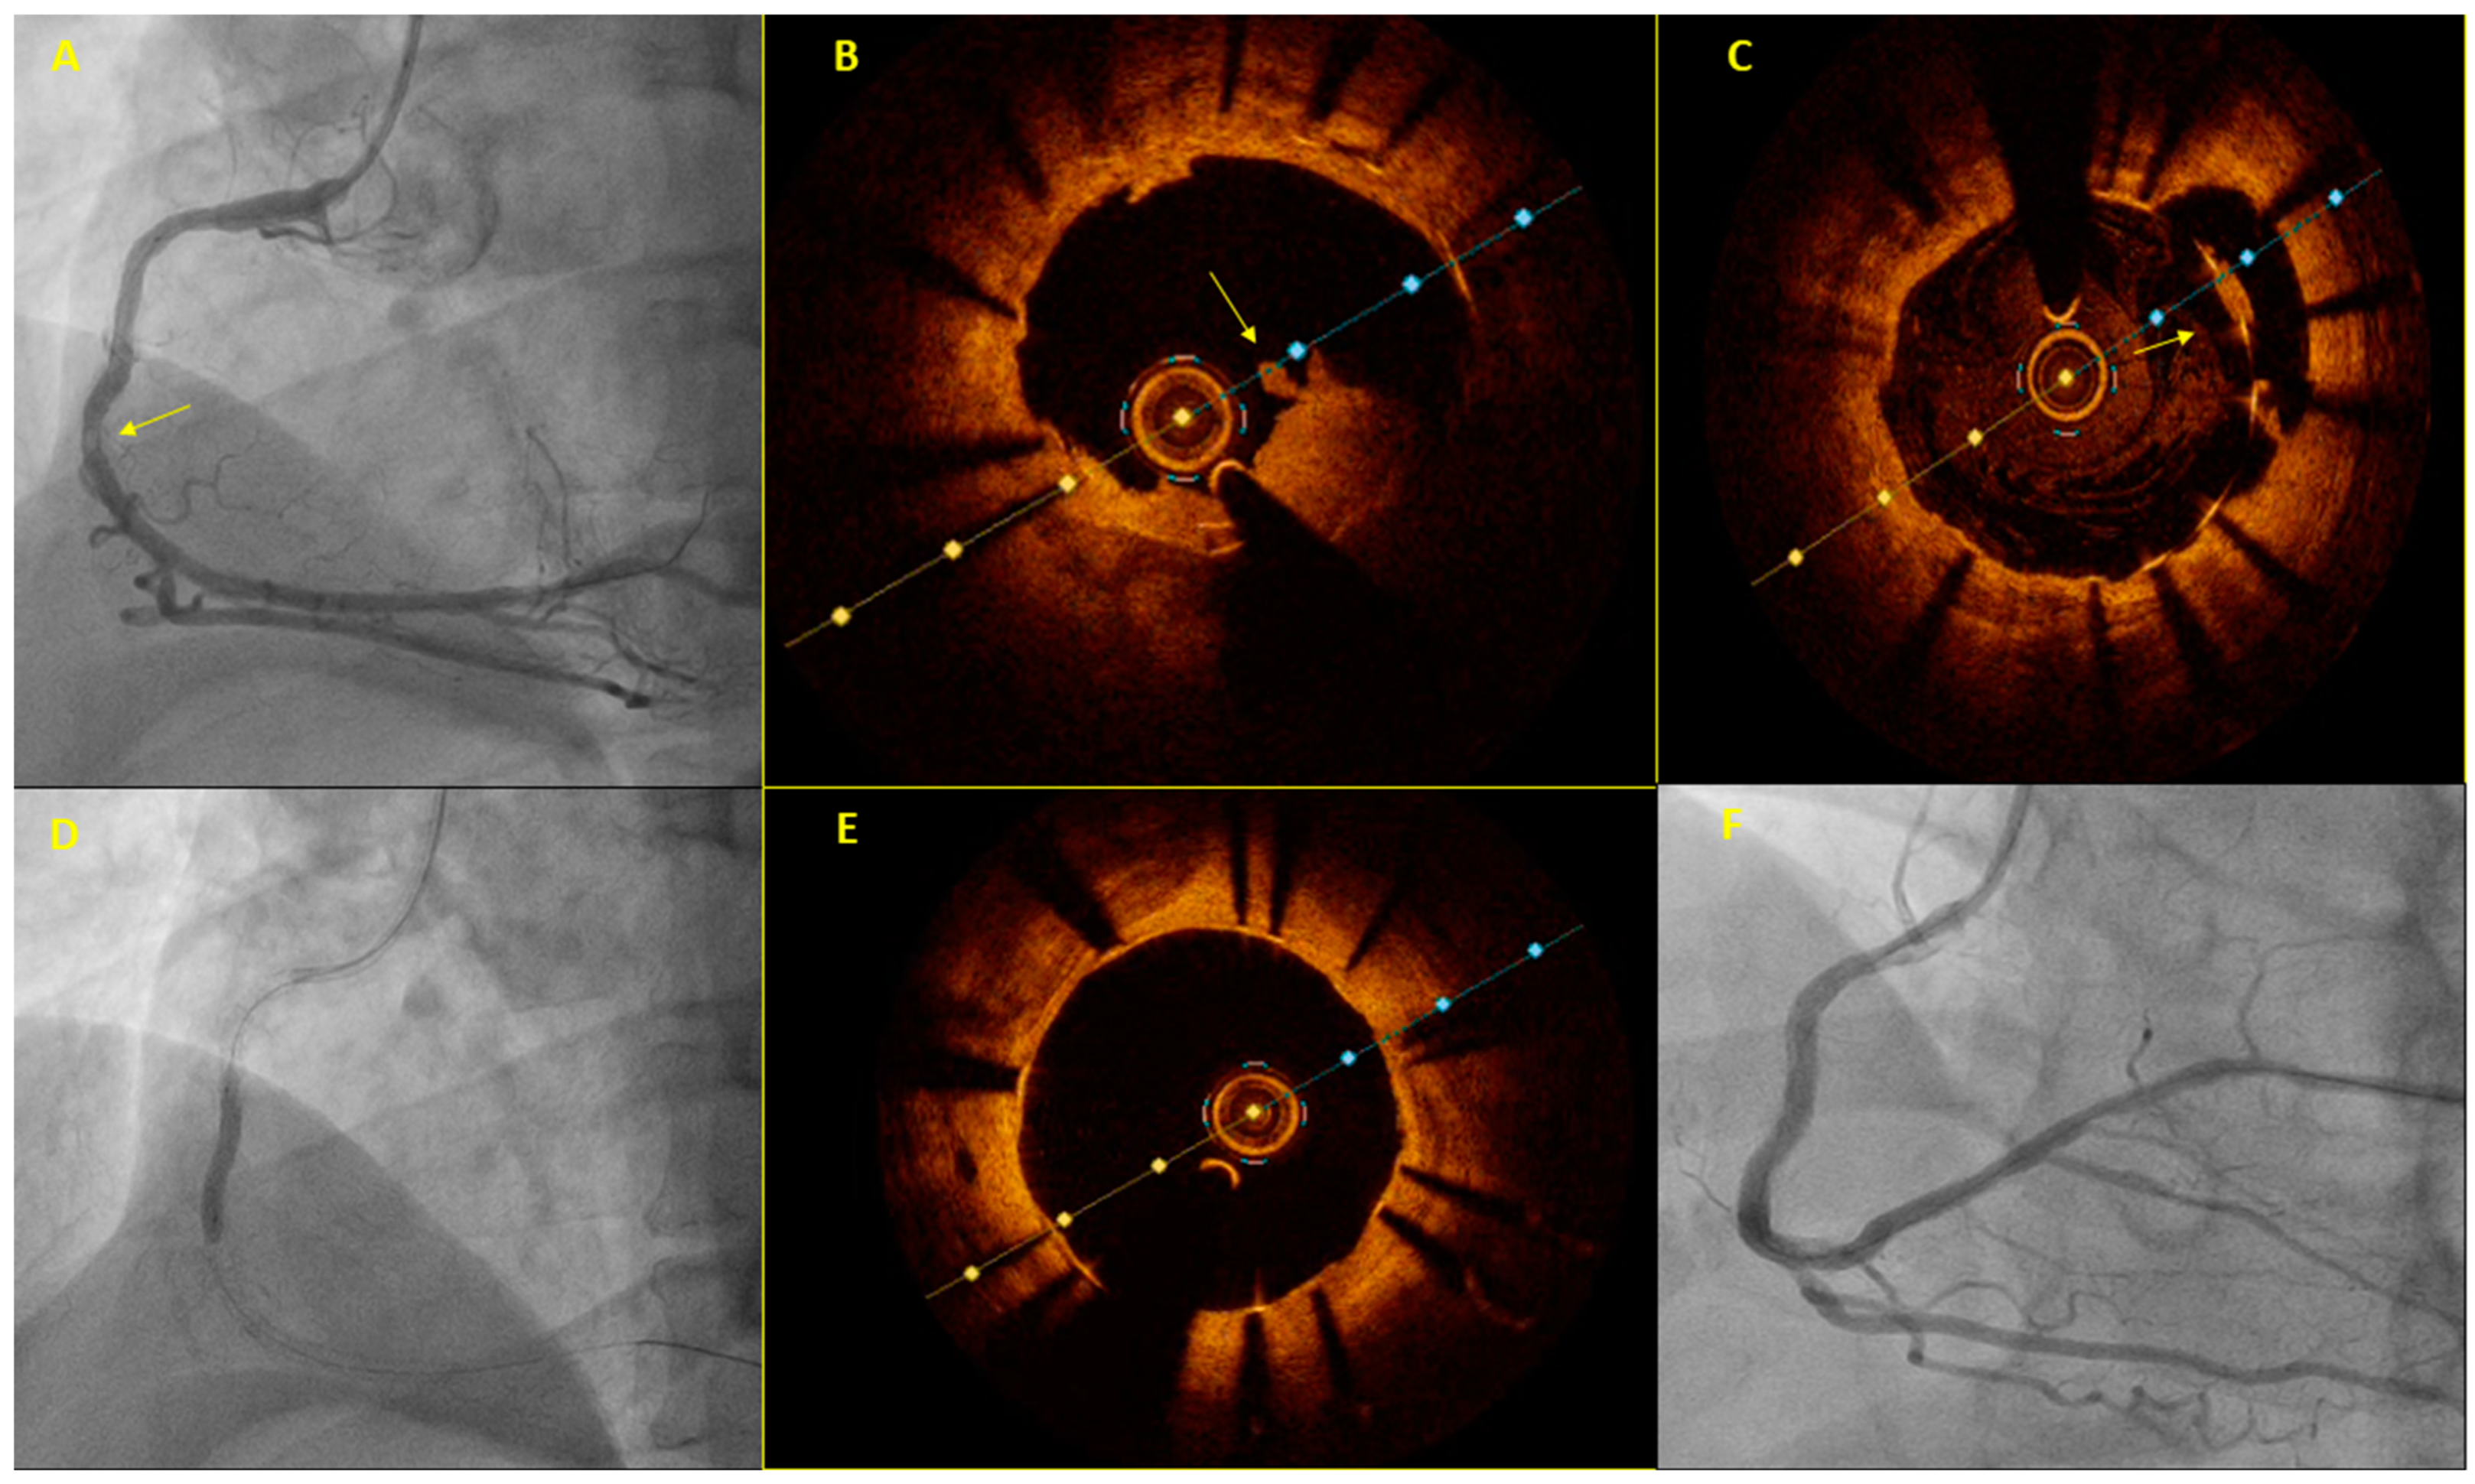

Figure 1.

A sixty-year-old patient was referred for primary PCI due to inferior STEMI. He had a stent implanted in the right coronary artery (RCA) 11 years earlier. The initial coronary angiography showed no significant stenosis in the coronary arteries. A careful review of the angiogram revealed an area of “haziness” in the mid-RCA (arrow, A). OCT illustrated the presence of a non-obstructive red thrombus in the corresponding RCA segment (arrow, B) within the previously implanted stent, which appeared to be underexpanded and malapposed (arrow, C). Dilation with a non-compliant 3.5 mm balloon and a drug-coated 3.5 mm Agent balloon followed (D). Repeat OCT showed a significantly better stent expansion and apposition (E) with an excellent final angiographic result (F).